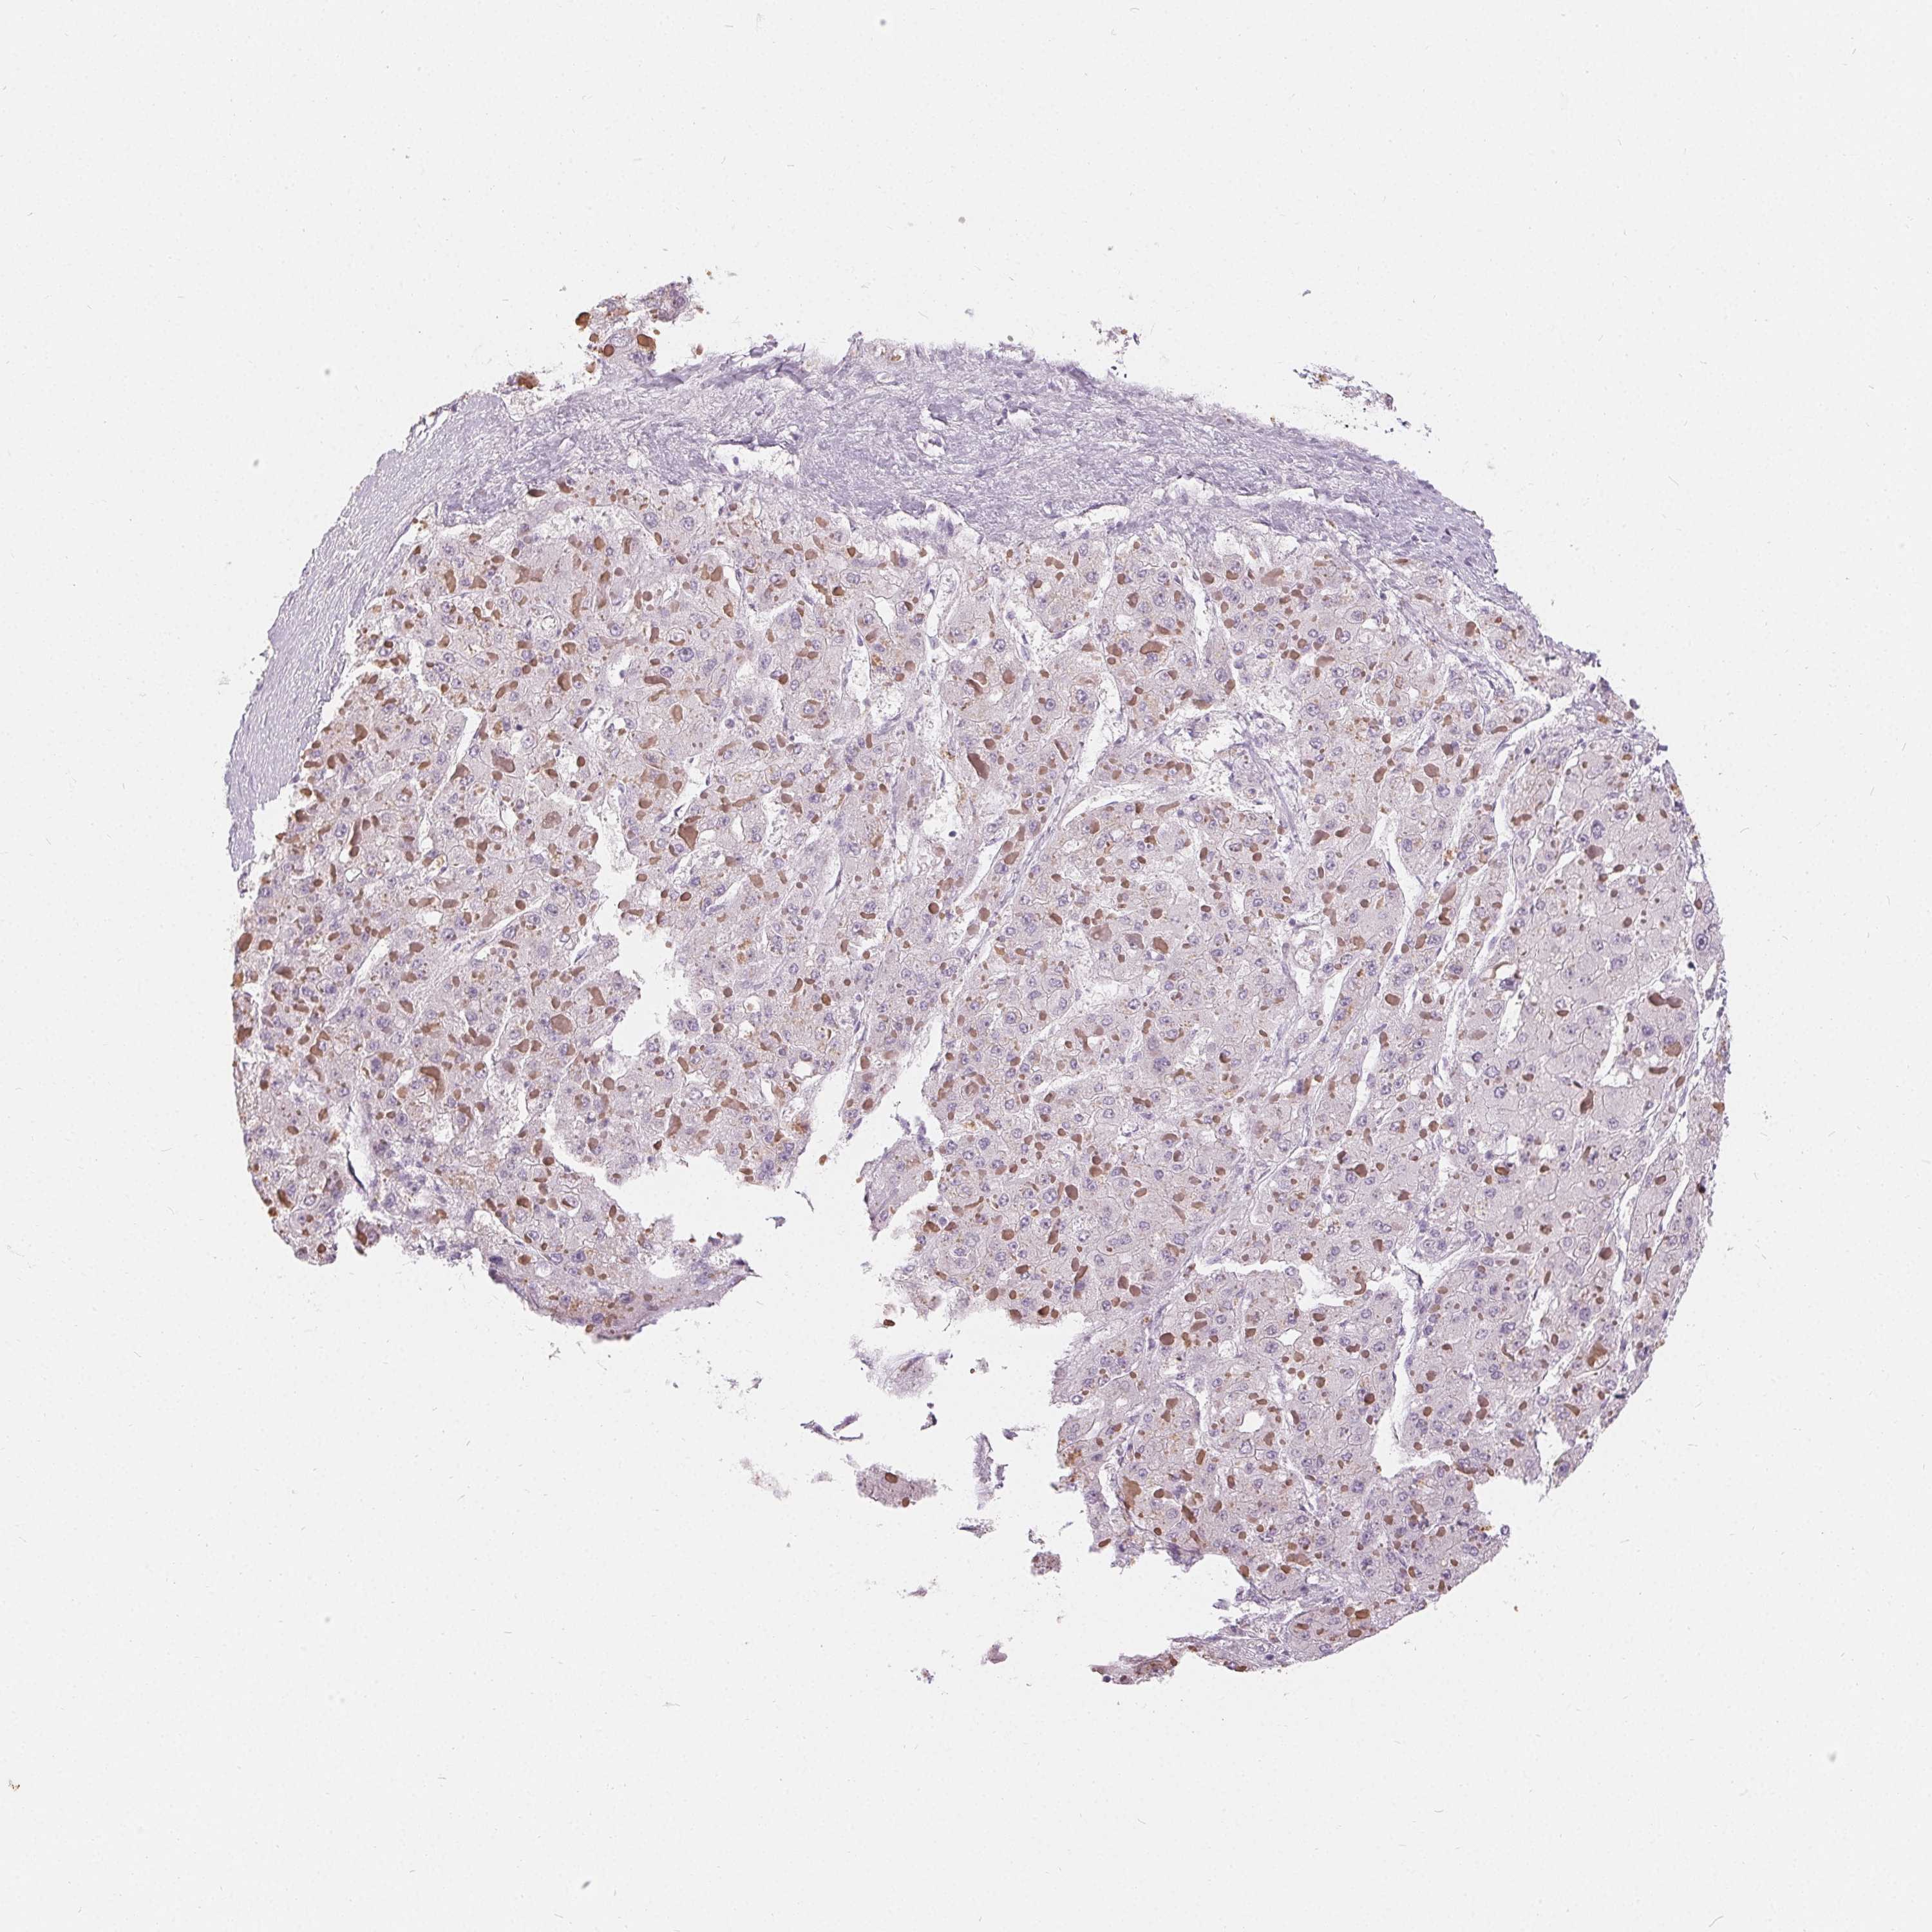

LIVER CANCER - Protein expressioni

A mouse-over function shows sample information and annotation data. Click on an image to view it in a full screen mode. Samples can be filtered based on level of antibody staining by selecting one or several of the following categories: high, medium, low and not detected. The assay and annotation is described here.

Antibody stainingi

Antibody staining in the annotated cell types in the current human tissue is reported as not detected, low, medium, or high, based on conventional immunohistochemistry profiling in selected tissues. This score is based on the combination of the staining intensity and fraction of stained cells.

Each image is clickable and will lead to virtual microscopy that enables deeper exploration of all samples and also displays staining intensity scores, fraction scores and subcellular localization as well as patient and tissue information for each sample.

Antibody HPA030180

Antibody CAB018632

Staining

High

Medium

Low

Not detected

Intensity

Strong

Moderate

Weak

Negative

Quantity

>75%

75%-25%

<25%

None

Location

Nuclear

Cytoplasmic/membranous

Cytoplasmic/membranous,nuclear

Carcinoma, Hepatocellular, NOS

Cholangiocarcinoma